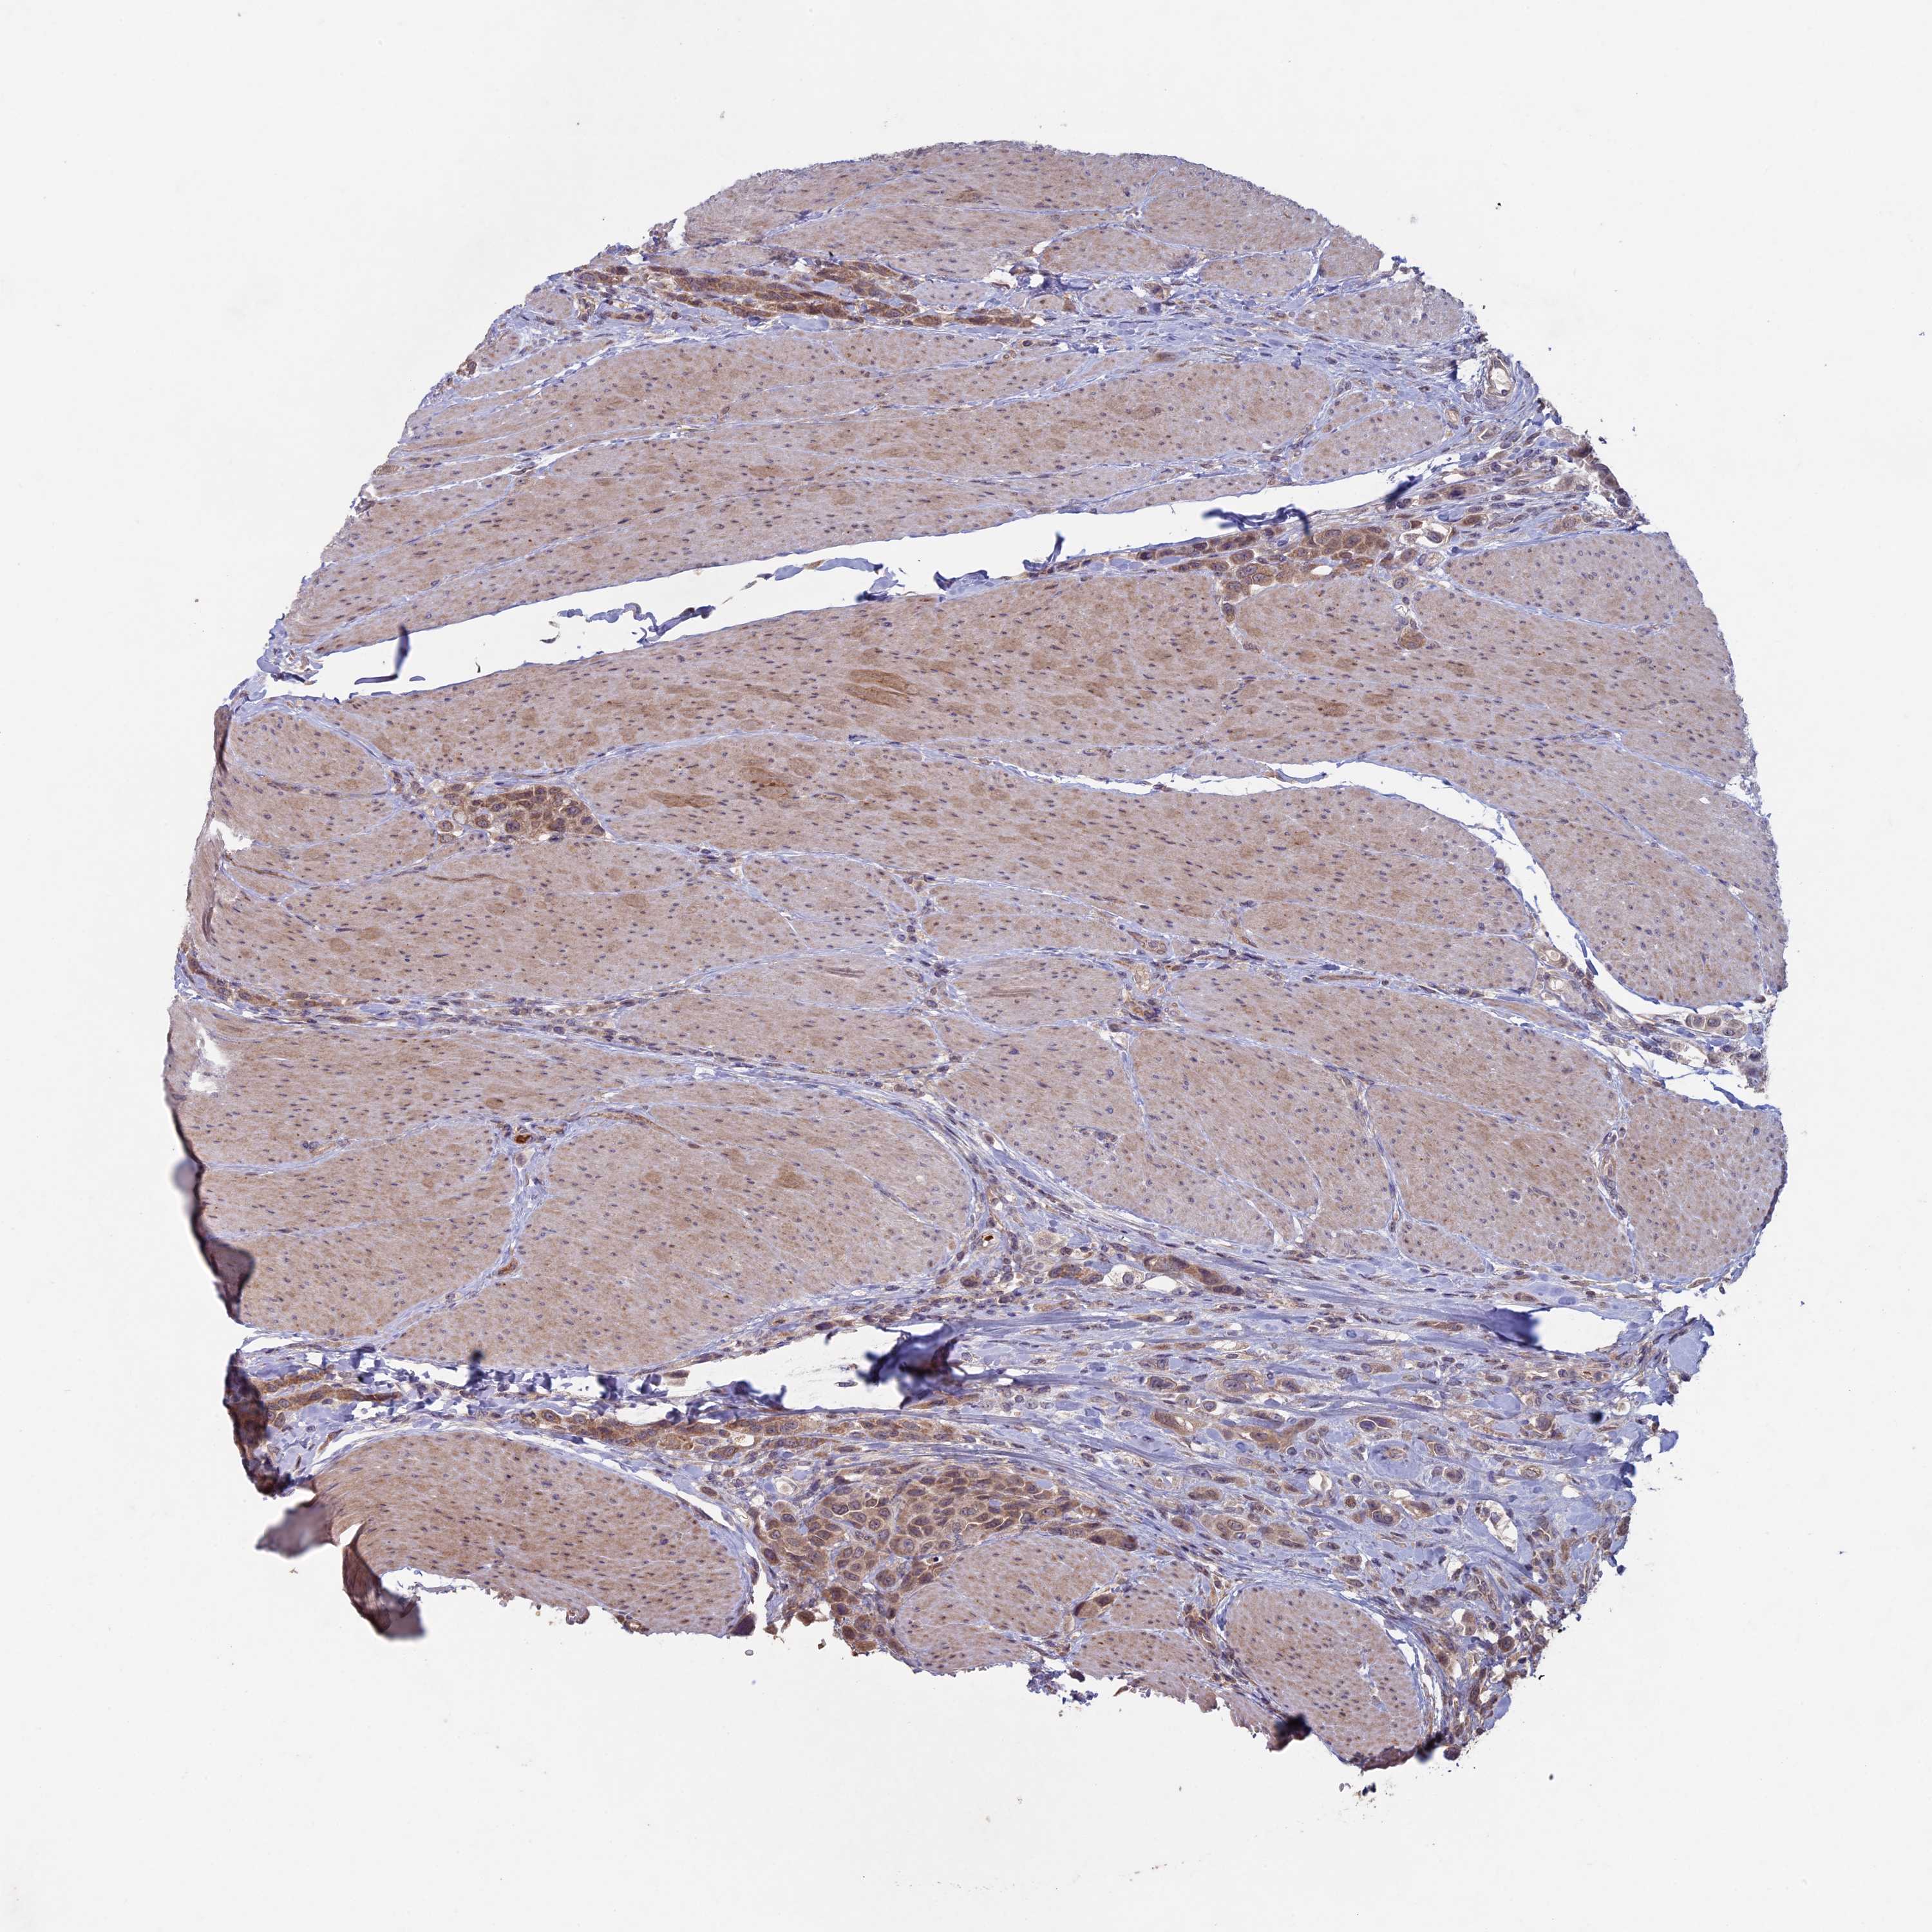

UROTHELIAL CANCER - Protein expressioni

A mouse-over function shows sample information and annotation data. Click on an image to view it in a full screen mode. Samples can be filtered based on level of antibody staining by selecting one or several of the following categories: high, medium, low and not detected. The assay and annotation is described here.

Note that samples used for immunohistochemistry by the Human Protein Atlas do not correspond to samples in the TCGA dataset.

Antibody stainingi

Antibody staining in the annotated cell types in the current human tissue is reported as not detected, low, medium, or high, based on conventional immunohistochemistry profiling in selected tissues. This score is based on the combination of the staining intensity and fraction of stained cells.

Each image is clickable and will lead to virtual microscopy that enables deeper exploration of all samples and also displays staining intensity scores, fraction scores and subcellular localization as well as patient and tissue information for each sample.

Antibody HPA039683

Antibody HPA040776

Urothelial carcinoma, High grade

Urothelial carcinoma, Low grade